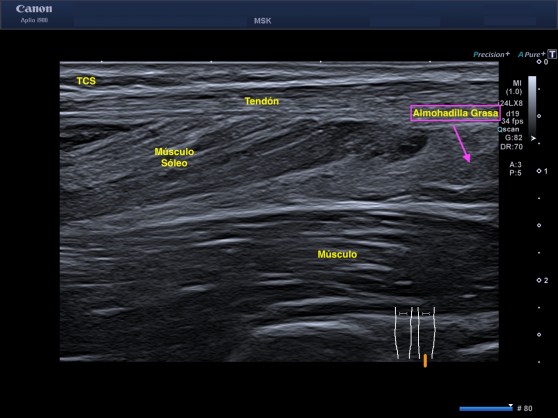

3. Tendón: Son bandas de tejido conectivo muy resistentes que se sitúan a cada extremo del músculo y que lo sujetan al hueso. Tiene una estructura de fibras muy marcadas fruto de la diferencia de ecogenicidad entre colágeno y endotendón que es hiperecogénica y el paratendón que es hipoecogénico.

8. Tejido Celular Subcutáneo: La grasa subcutánea distribuida por toda la anatomía. Compuesta de lobulillos, hipoecogénicos separados por tejido conectivo paralelos a la piel que son hiperecogénicos.

10. Almohadillas Grasas: Son áreas compuestas de células grasas, rodeadas de tabiques fibrosos tisulares. La almohadillas grasas están tremendamente irrigadas con capilares y presentan numerosas terminaciones nerviosas, su aspecto es hiperecogénico y heterogéneo.